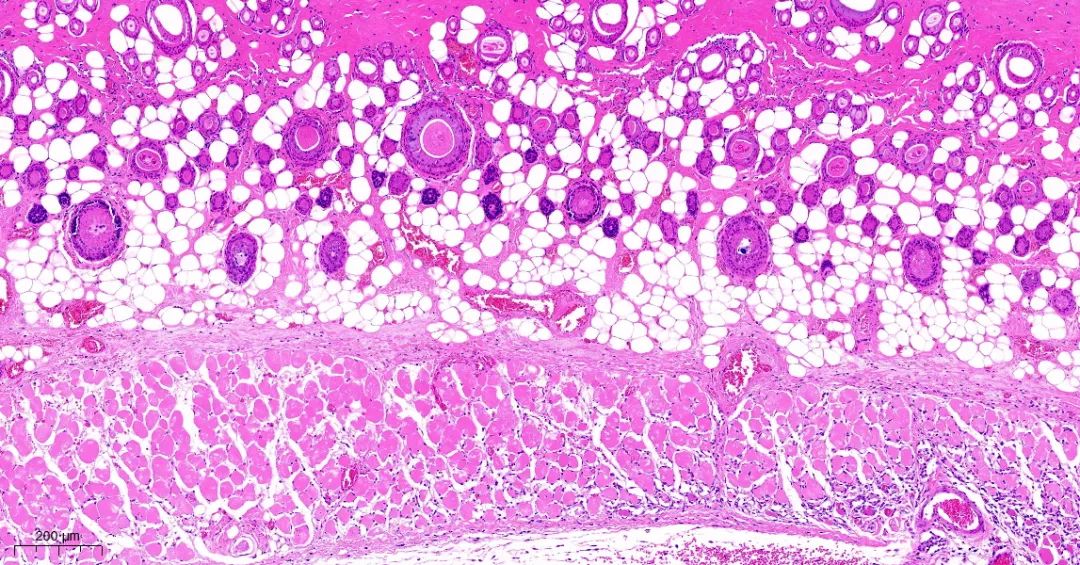

取正常对照组及模型组大鼠背部皮肤标本,常规固定,石蜡切片,HE染色,观察皮肤组织学变化。

模型1组皮组织切片对比

模型2组皮组织切片对比